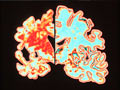

Brain Health Resource Center

Tips, tools and explainers on brain health from AARP | En español